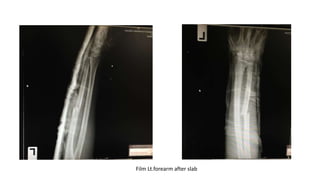

Film Lt.forearm after slab

- Immobilization with posterior long arm slab

- Admit for surgery(ORIF)